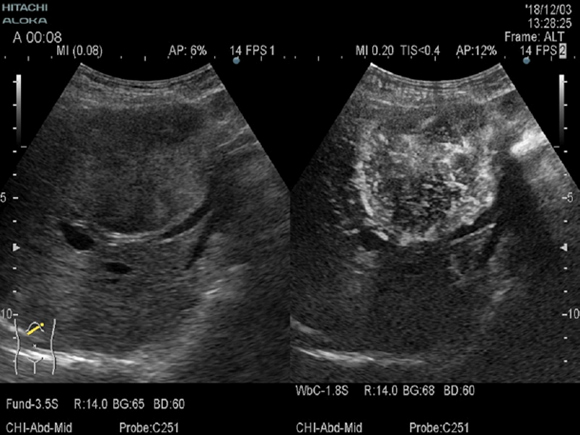

ソナゾイド造影エコー

造影剤を投与し体内の血液の流れを明瞭に抽出することができるため、肝臓などの腫瘤のより繊細な性状を検査することができます。検査時間は1時間ほどです。※玉子アレルギーの方はこの検査はできません。

造影剤を静脈注射して30秒から1分後の早期血管相における造影剤の染まり(濃染)と10分後(クッパ―相)の造影剤の抜けの組合せで診断します (下図)。早期相にて動脈血流が豊富な肝腫瘍がはっきりと抽出されています。